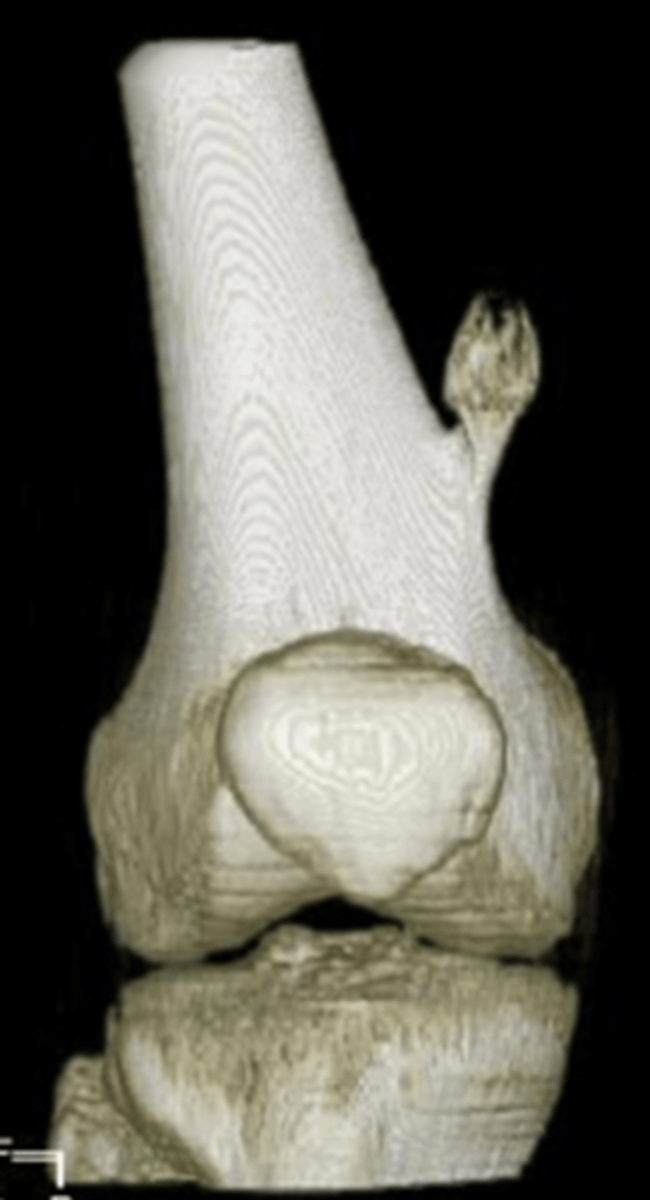

Solitary osteochondroma

- Most common benign skeletal growth or tumor

- 50% of all benign bone tumors

- 10-15% of all primary bone tumors

- 75% <20 y.o.

- M:F, 2:1

- Malignant transformation <1%

- Mostly asymptomatic

- Painless, hard mass

- Stalk may fracture

- Pain and rapid growth = malignant transformation

State the clinical features of solitary osteochondroma

Pedunculated

_____ solitary osteochondroma:

- Metaphyseal

- Thin, elongated stalk

- Cortex and medulla continuous

- Calcified cap

- Projects away from joint

- Lucent when en face (on end)

Cartilage cap

What is this?